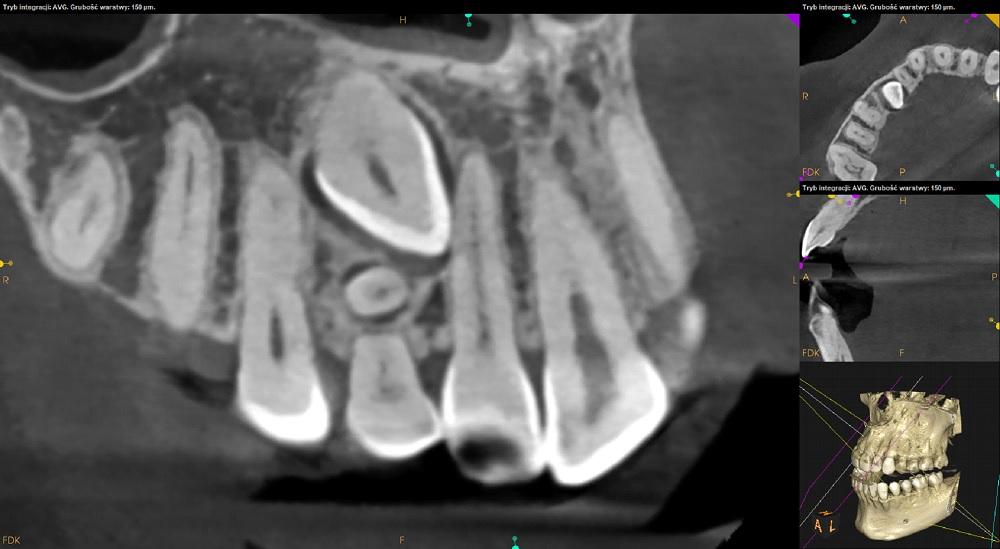

Tomografia szczęka i żuchwa.

Ząb 13 – zatrzymany. Położony pionowo skośnie, koroną skierowany w stronę mezjalną i podniebienną. Zrotowany w stronę dystalną.

Korona zęba 13 przylega do korzenia zeba 12 – resorpcja korzenia niewidoczna. Wierzchołek korzenia zęba 13 zagięty.